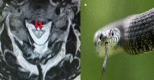

Signs of Nature in Spine Radiology

As medical science developed over time, we have relied on natural imagery to help us recognise and remember things. In this review article, we will be discussing some radiological signs named because of their resemblance to the occurrences in the natural world.